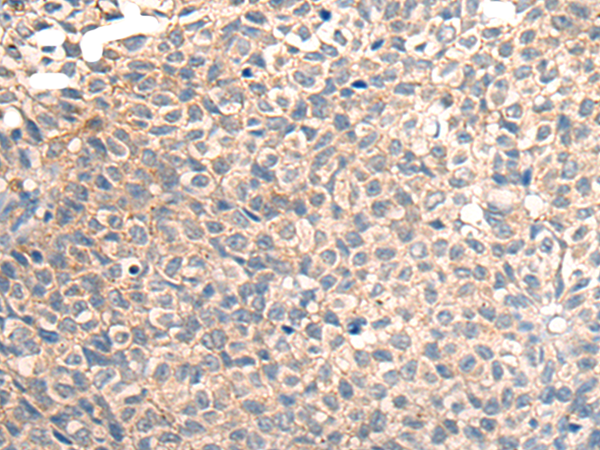

分类: 科研抗体货号: P06210别名:应用: WB,IHC反应种属: Human, Mouse, Rat